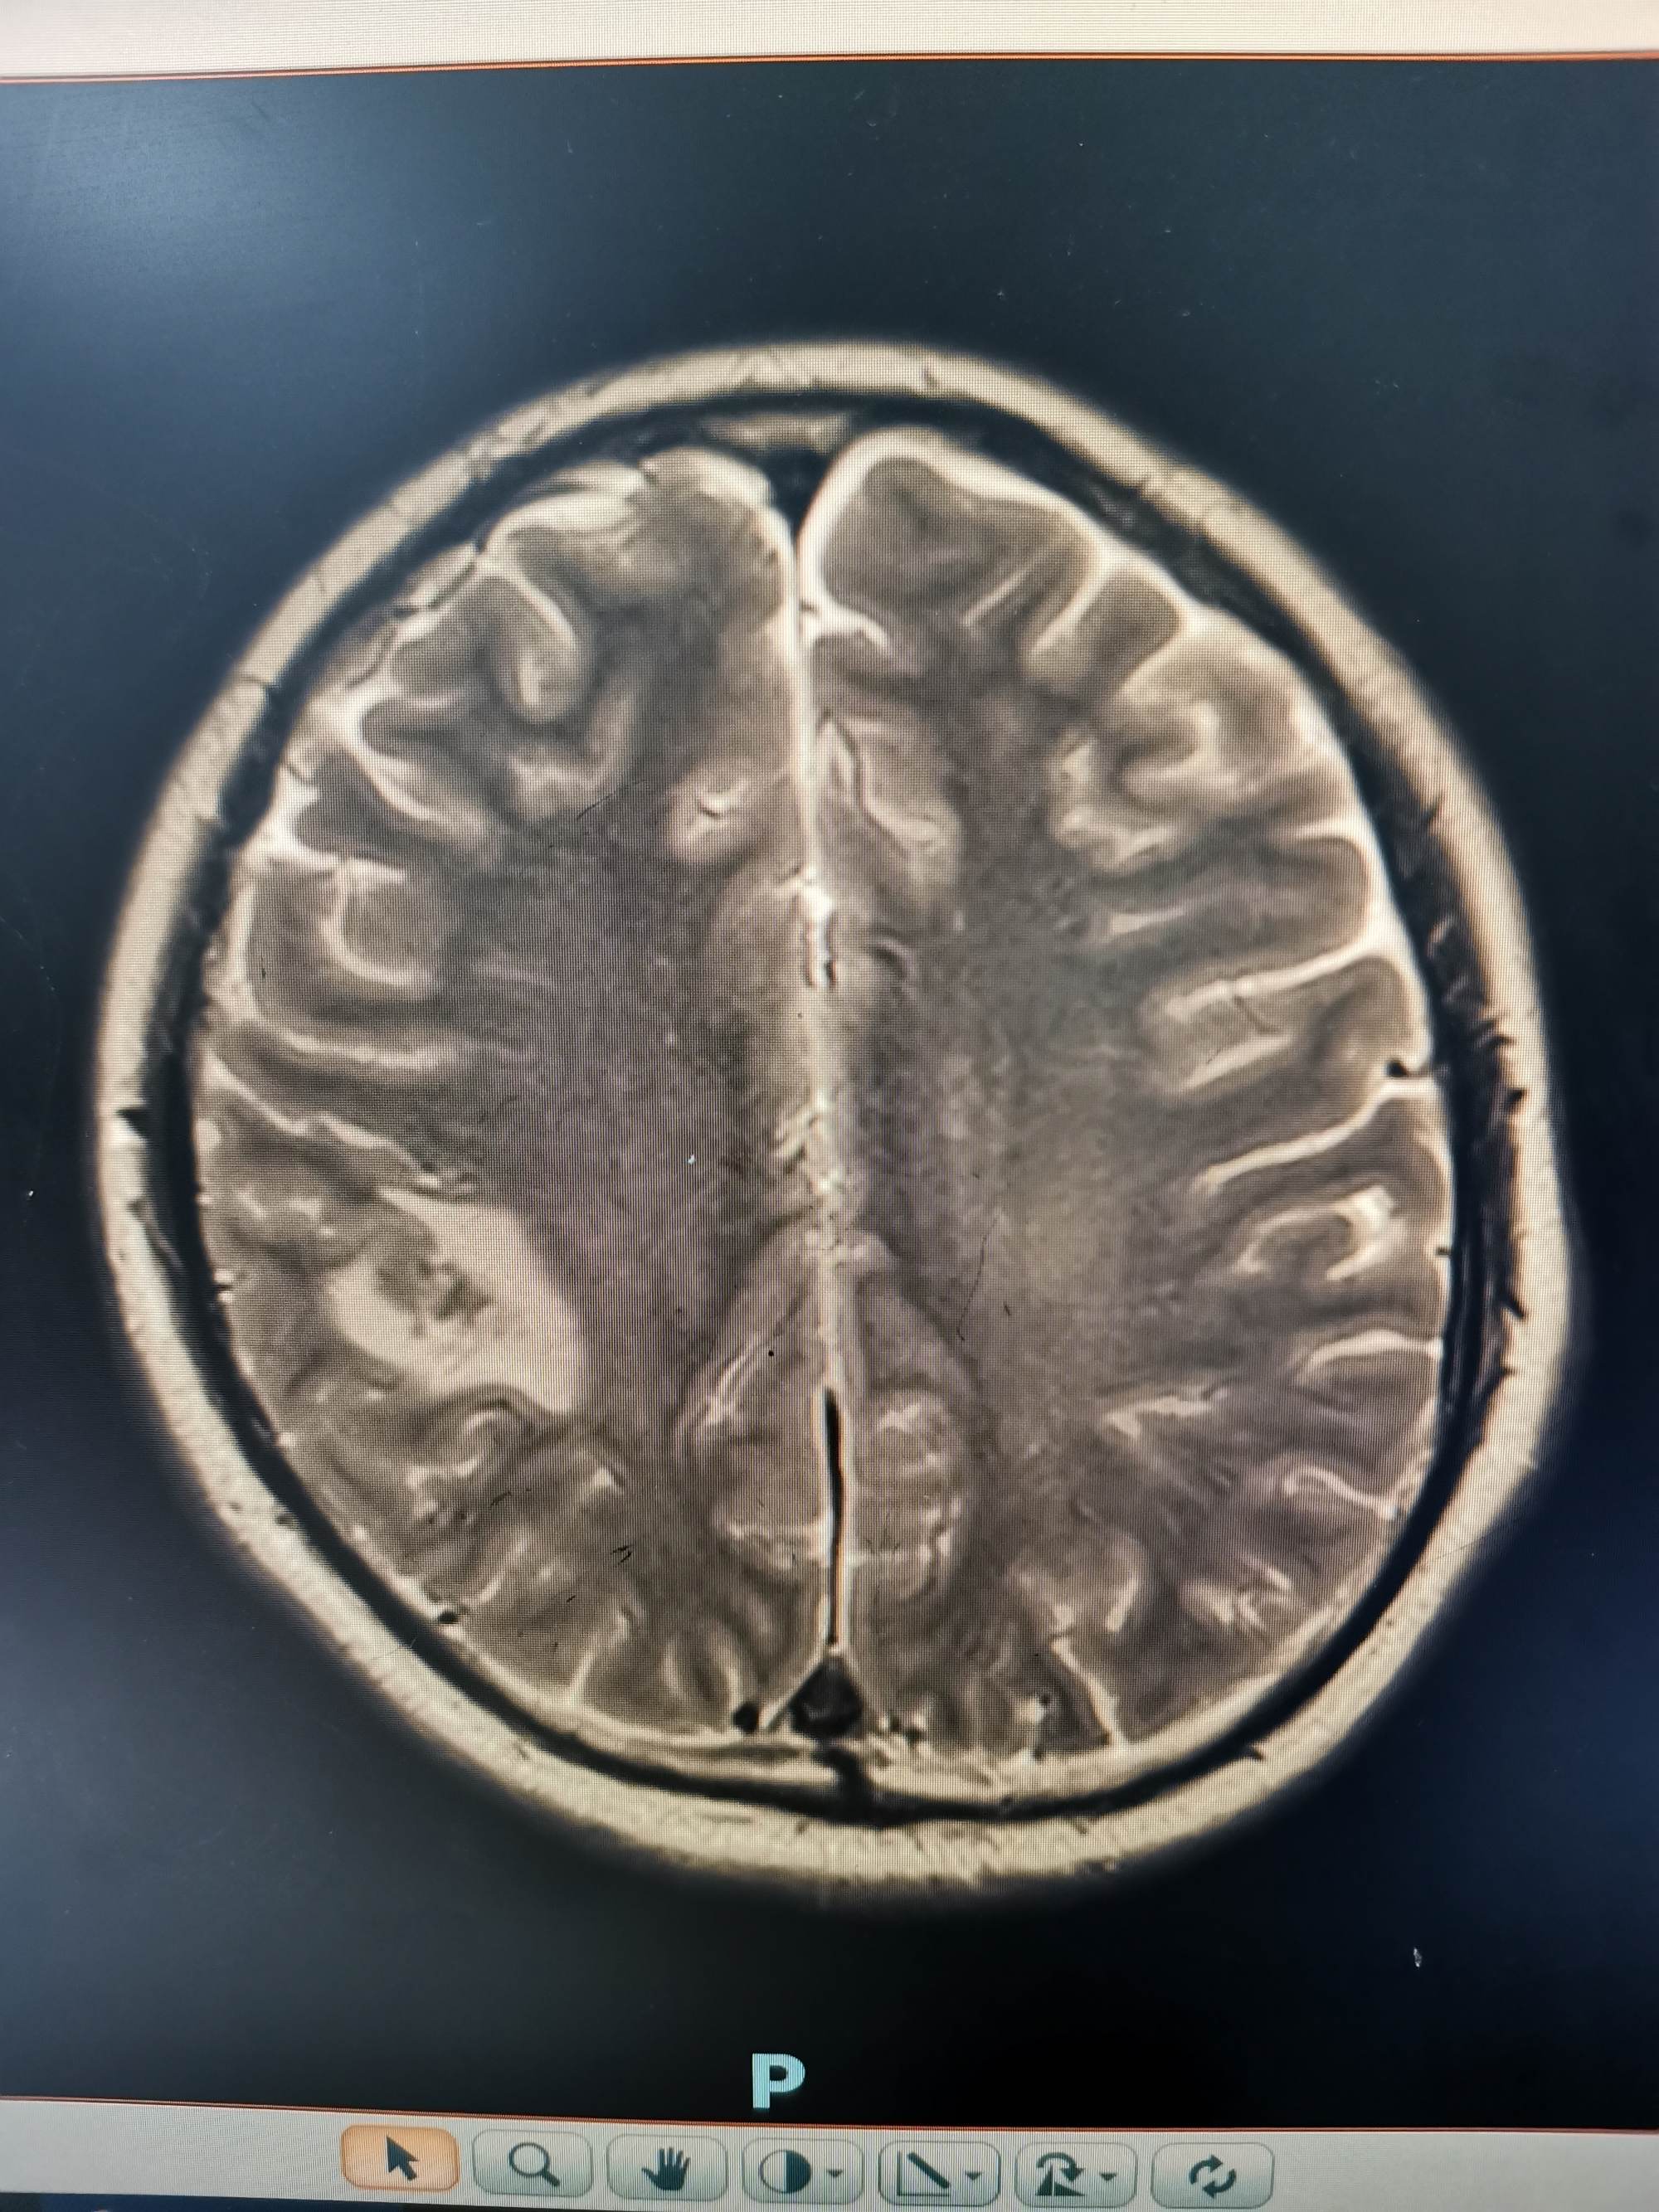

外院磁共振提示右侧顶叶病变

入院后急查头颅磁共振发现顶叶又新发两个病灶。

磁共振发现顶叶又新发两个病灶